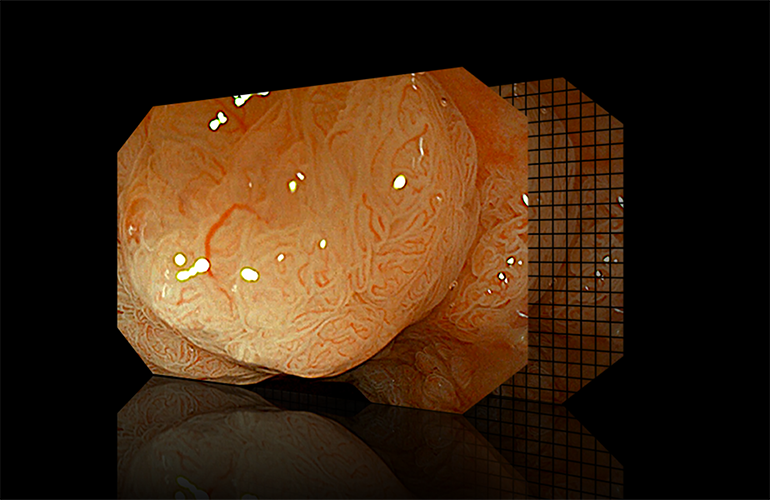

CBI aqua способствует лучшей визуализации структуры слизистой оболочки. |  |

1080P Full HD

Оснащён датчиком изображения с высоким разрешением, в сочетании с гастроскопами и колоноскопами позволяет получать изображения качества 1080P.

- CBI aqua — улучшенное отображение структуры слизистой.